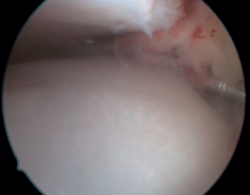

Arthroscopic diagnosis

The confirmation of AAI is made by direct vision during arthroscopic examination (Figure 4). This technique allows us to visualise the entire joint, assess the state of the articular cartilage and ligaments, detect the presence of capsular adhesions, synovitis, synovial thickening, loose bodies, etc. It also allows us to carry out functional tests to reveal possible associated instabilities or to assess how the soft tissues causing pain suffer impingement. In our experience, the presence of ATFL lesions is very frequent.

Figure 4. Soft tissue anterolateral impingement in a patient with concomitant anterior talofibular ligament injury who underwent arthroscopic repair associated with resection of the impingement.